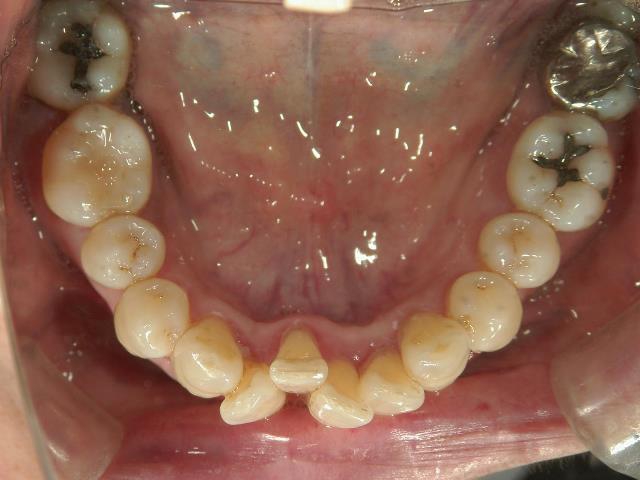

矯正歯科 治療前矯正歯科 治療前

64歳女性 浜松市中区在住

治療期間 7カ月

矯正_灰色.pngno.12_5333_治療前_下.jpg矯正_灰色.png